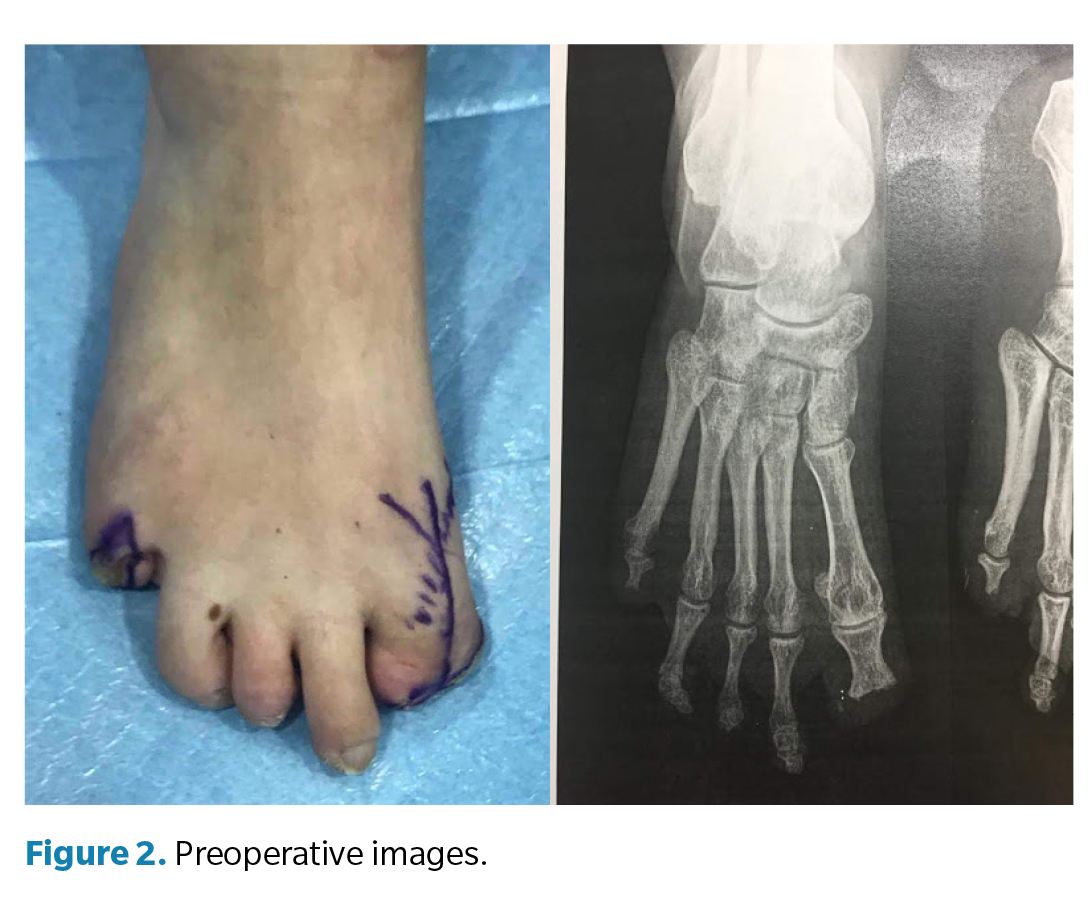

La cirugía (Figura 3) se realizó en marzo de 2022 bajo anestesia regional mediante bloqueo poplíteo posterior con sedación consciente supervisada por anestesiólogo. Se administró profilaxis antibiótica con cefazolina 2 g por vía intravenosa 30 min antes de la incisión y se utilizó torniquete neumático a nivel del tobillo, con presión controlada (a 250 mm Hg) y tiempo de isquemia limitado a 45 min. Se efectuó un abordaje dorsal longitudinal sobre la primera articulación metatarsofalángica, respetando las estructuras neurovasculares. Se identificaron los restos óseos irregulares de la falange proximal y se realizó su resección completa, seguida de remodelado de los márgenes óseos hasta obtener superficies regulares y viables. Posteriormente, se prepararon las superficies articulares de la primera metatarsofalángica mediante fresado y curetaje hasta lograr una base sangrante adecuada para la artrodesis. La posición de fusión se determinó intraoperatoriamente mediante pruebas de carga, fijando el hallux en aproximadamente 10° de dorsiflexión respecto al plano del suelo, con el fin de optimizar la propulsión y evitar la sobrecarga plantar en el muñón residual. La fijación definitiva se realizó con 1 tornillo canulado tipo Herbert, verificándose estabilidad intraoperatoria y correcta alineación mediante fluoroscopia (Figura 4). El procedimiento concluyó sin incidencias, con hemostasia cuidadosa y cierre por planos.

El postoperatorio incluyó curas secas periódicas y seguimiento funcional progresivo. A los 3 meses de la intervención se constató resolución completa del dolor y mejoría significativa en la calidad de la marcha. A los 6 meses la paciente presentó recupe­ración funcional satisfactoria, por lo que se procedió al alta médica temporal. Posteriormente se confeccionaron prótesis digitales de silicona personalizadas para ambos pies, destinadas a mejorar la simetría podológica, la distribución de cargas y la aceptación psicosocial. En el seguimiento a los 12 meses, la paciente se mantenía asintomática, con consolidación radiográfica completa de la artrodesis, alineación correcta del primer radio y marcha estable sin limitaciones, confirmando el éxito funcional del procedimiento.